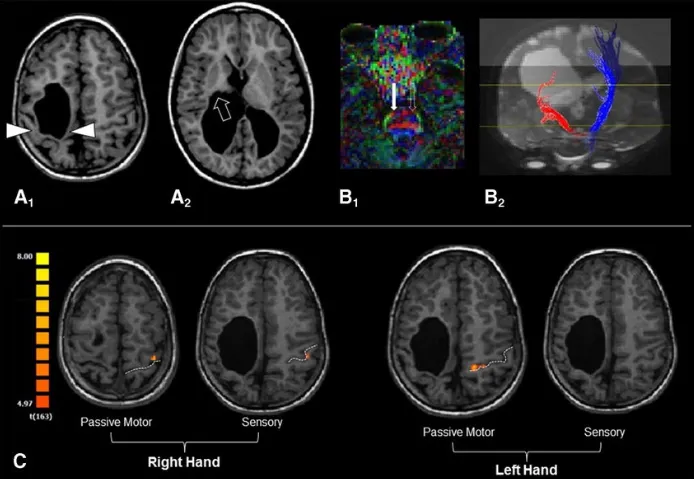

图5:患者感觉运动结构损伤与功能重组的多模态MRI综合评估。轴位T1-MPRAGE图像显示右侧脑室周围白质软化病变,病变广泛累及中央前回与中央后回,并延伸至丘脑后部及内囊后肢。在DTI微观结构分析中,右侧皮质脊髓束纤维与健侧相比显示不清;纤维束追踪重建亦显示右侧纤维束数量和走行长度明显少于左侧,两侧存在显著不对称。功能评估结果叠加于解剖MPRAGE图像之上显示:右手被动运动及感觉任务均在左侧中央前回与中央后回引发了明确激活;左手被动运动任务在同侧左侧中央前回水平亦触发了激活,但感觉任务未见显著激活;所有任务条件下,右侧大脑半球均未检测到显著激活,图像以放射学惯例方向呈现。